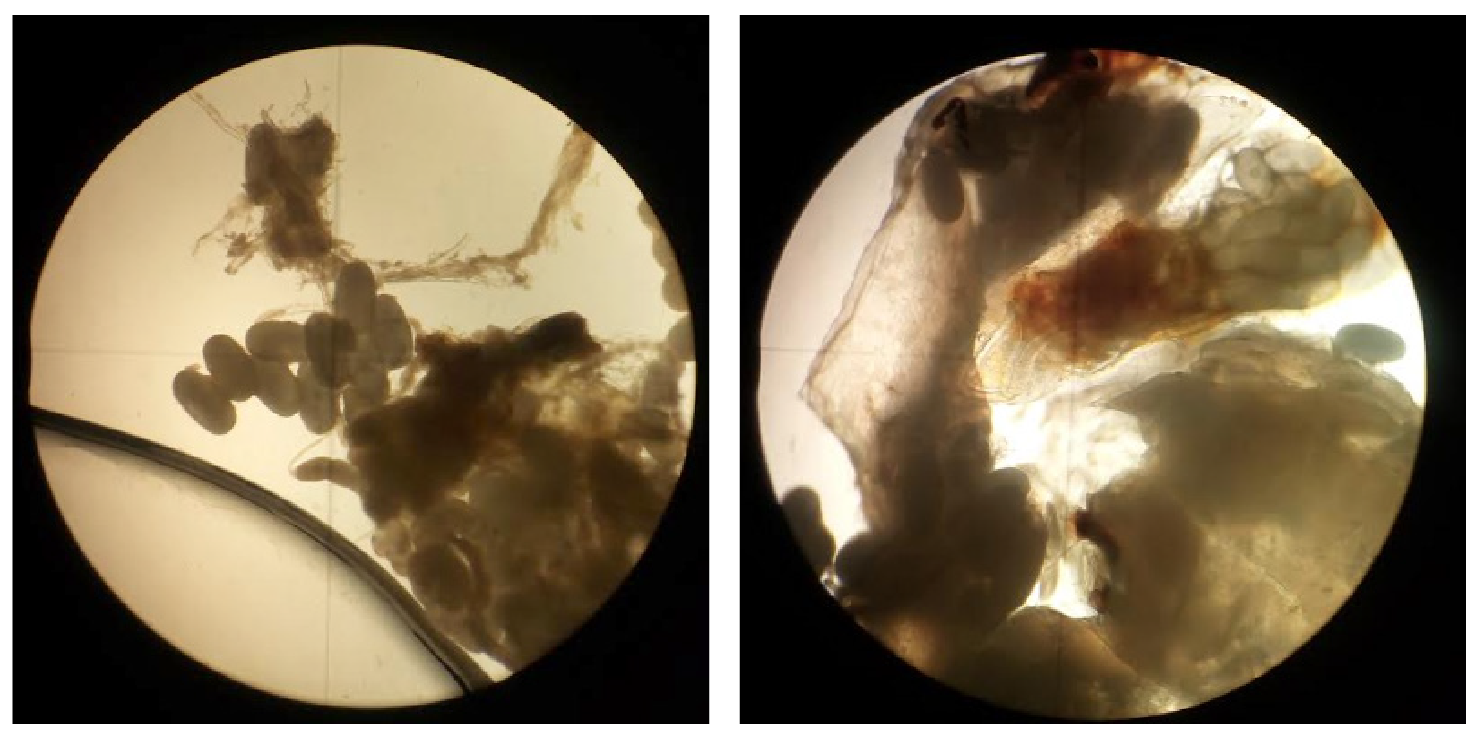

Con base en las características clínicas, se diagnosticó tungiasis, se le administró una dosis única de ivermectina de 200 μg/kg y se le hizo la extracción quirúrgica de las lesiones, las cuales se enviaron a estudio. El análisis parasitológico confirmó la presencia de restos de hembras adultas de T.penetrans, con huevos en su interior (figuras 4 y 5).

Figuras 4 y 5 Restos de Tunga penetrans. Se observan el vientre y la cloaca del parásito, con presencia de huevos en el interior y exterior. Sin coloración, 4X.